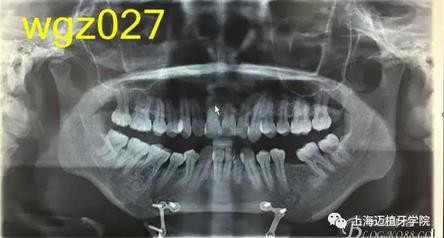

曲面斷層片:28顆恒牙,LL6缺失,牙槽骨均位于釉牙骨質(zhì)界以下,LR6、LL7近中牙槽骨角型吸收,頦部可見(jiàn)成型術(shù)鈦合板。左側(cè)升支較右側(cè)粗。